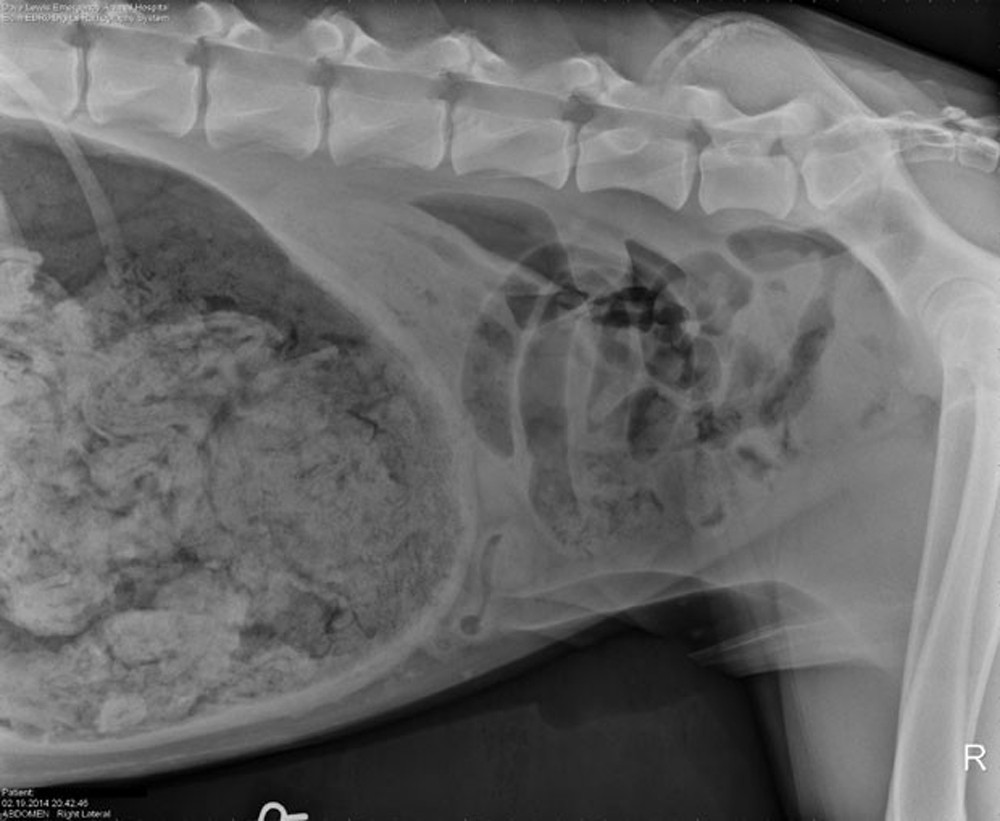

Um exame de raio-X acabou revelando o que vinha provocando as dores no animal. O raio-X mostrou uma grande "quantidade de material estranho" no estômago do cão.

O raio-X rendeu à clínica um prémio US$ 500 em um concurso promovido pela revista "The Veterinary Practice News", que elegeu as imagens mais bizarras de objetos comidos por animais de estimação.